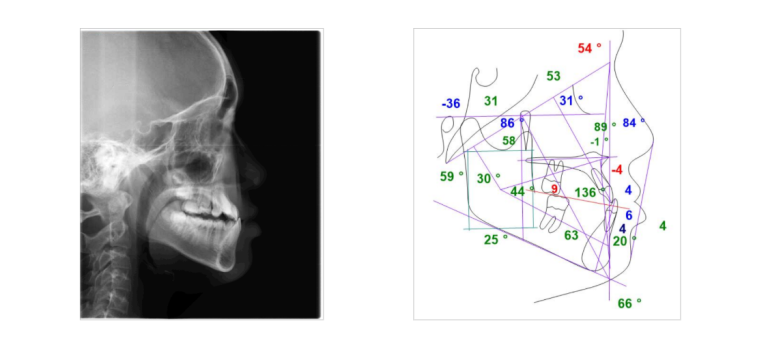

Các dấu hiệu thẩm mỹ là rõ ràng nhất: khi nhìn nghiêng, khuôn mặt có dạng lưỡi cày hoặc gãy khúc với cằm nhô ra rõ rệt. Phân tích phim X-quang sẽ cho thấy các chỉ số xương hàm trên và dưới bị sai lệch nghiêm trọng, thể hiện sự chênh lệch lớn về kích thước và vị trí.